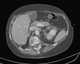

Left inferior vena cava

The inferior vena cava (or IVC) is a large vein that carries the deoxygenated blood from the lower and middle body into the right atrium of the heart. It is formed by the joining of the right and the left common iliac veins, usually at the level of the fifth lumbar vertebra.The inferior vena cava is the lower ("inferior") of the two venae cavae, the two large veins that carry deoxygenated blood from the body to the right atrium of the heart: the inferior vena cava carries blood from the lower half of the body whilst the superior vena cava carries blood from the upper half of the body. [Source: Wikipedia ]